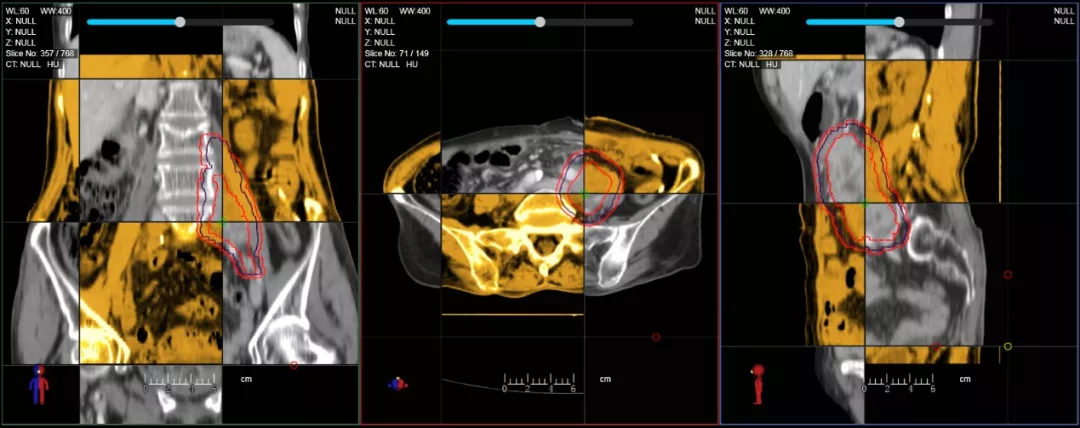

CT-IGRT配準(zhǔn),除骨性標(biāo)記外,還能以器官、軟組織等作為參考,真正找到配準(zhǔn)目標(biāo)

個體化自適應(yīng)放療

一體化CT-linac讓自適應(yīng)放療ART概念變?yōu)楝F(xiàn)實?;颊呷煶虪顟B(tài)監(jiān)控,適時在線調(diào)整治療計劃,精準(zhǔn)控制治療劑量,為患者動態(tài)定制個體化治療方案。uAI賦能智能勾畫和自動計劃,秒級勾勒靶區(qū)和危及器官,大幅縮短自適應(yīng)放療時間。

在線自適應(yīng)放療流程示意圖